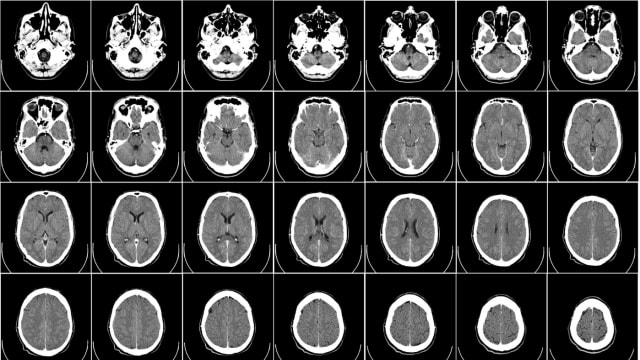

Ein AI-System in Australien konnte jetzt voraussagen, wer die nächsten fünf Jahre nicht überlebt – alleine aufgrund von CT-Scans. Wenn das keine brisanten Folgen hat.

Die Studie, veröffentlicht in «Nature Scientific Reports», dreht sich zuerst einmal um Radiologie. Erst beim zweiten Blick ahnt man, welche gesundheits- und gesellschaftspolitische Wucht hinter den Aussagen stecken könnte. Forscher der Universität Adelaide gingen dabei der Frage nach, wie gut so genannte Deep-Learning-Programme inzwischen CT-Scans auswerten und deuten können.

Und zwar fütterten sie das System zuerst mit abertausenden Bildern aus früheren Jahren – sowie der Information, welcher Mensch zu welchem späteren Zeitpunkt gestorben war. In einem weiteren Schritt nahmen sie erneut historische Aufnahmen von Patienten im Alter über 60. Dann liessen sie das Programm – in der Fachsprache: ein konvolutionelles neuronales Netzwerk – aufgrund des quasi gelernten Wissens interpretieren, wie die gesundheitliche Entwicklung dieser Menschen weiter verläuft.

Heraus kam, dass das System bei über zwei Dritteln der Menschen richtig vorhersagte, wer in den fünf Jahren danach sterben würde; konkret lag die Quote bei 69 Prozent.

Das System wurde also fähig, die Erscheinungen und das Auftreten zahlreicher Krankheiten in CT-Scans zu sehen, zu deuten und sich dann quasi die Konsequenzen zu berechnen. Am präzisesten waren die Prognosen bei Patienten mit schweren chronischen Krankheiten wie Lungenemphysemen und Herzinsuffizienz.

Das Team um den Radiologen Luke Oakden-Rayner hofft nun, dass dies lediglich ein erster Schritt war: Das Testprogramm hatte keinen Zugriff auf viele Informationen, welche jeder Arzt hat, und die ihm helfen, präzise Befunde zu erstellen. Es erreichte seine Genauigkeit, obwohl es nicht mal Alter und Geschlecht der auf den CT-Bildern erfassten Personen wusste.

Dabei geben die Forscher zu, dass sie teils nicht wussten, welche Aspekte ihr Programm in den einzelnen Fällen dazu verleitete, die Lebenserwartung zu prognostizieren – oder anders: Was Doktor Deep-Learning-Computer da eigentlich genau sah, war gar nicht so klar. Aber der digitale Diagnostiker konnte jedenfalls ziemlich gut sehen.